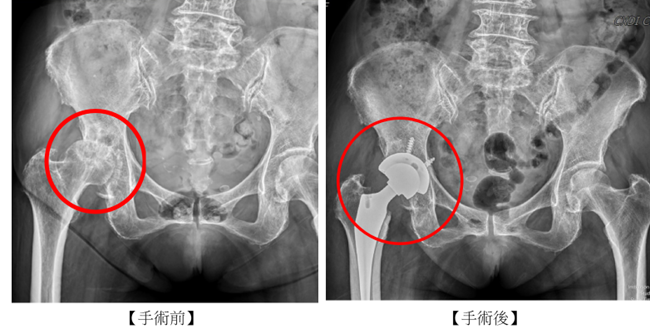

圖說一、手術前(左圖紅色圓圈處),X光可見右側關節軟骨嚴重磨損、關節間隙消失。術後(右圖紅色圓圈標示處)微創正前開人工髖關節置換(DAA)成功解除劇烈疼痛造成的走路不便。